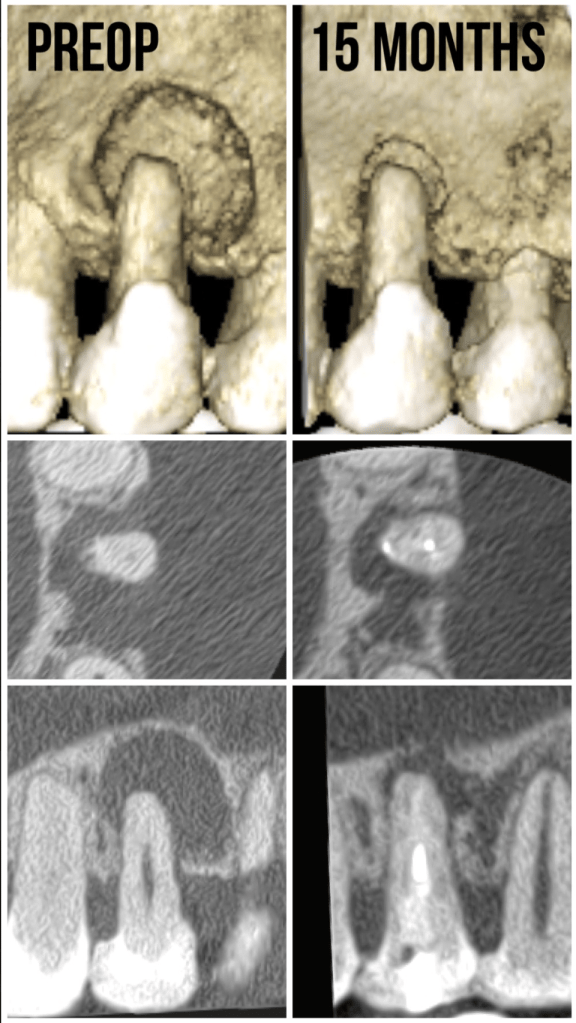

Casos con curación

Gran lesion algaba 6 meses